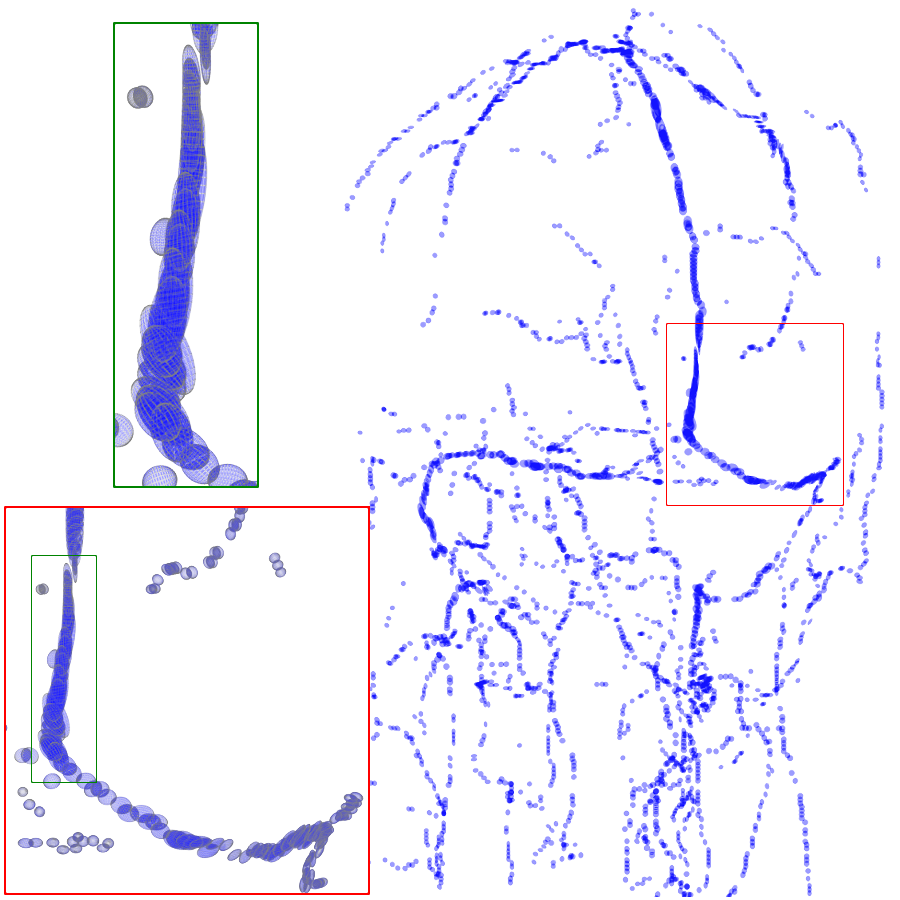

3.2 Connected Geodesic Paths as Vascular Tree

Representative examples of degraded synthetic images from SVT and the respective GT are shown in fig. 4 together with the connected graphs extracted by VTrails. Analogously, the same set of images are reported for the real images TOF and CTA in fig. 4. Qualitatively, the extracted set of connected geodesic paths shows remarkable matching with the provided GT in all cases. First, we verify the acyclic nature of the graph. We found no cycles, degenerate graphs and unconnected nodes, meaning that the extracted connected geodesic paths represent a connected geodesic tree. Precision and recall are then evaluated for the identified branches. Also, error distances are determined as the connected tree’s binary distance map evaluated at GT. Average errors () precision and recall are reported (meanSD) in table 1. Note that no pruning of any spurious branches is performed in the analysis.

| Synthetic Vascular Trees (SVT) [10] | Clinical Angiographies | ||||||

| Image | GT | VTrails | Image | GT | VTrails | ||

| N1 |  |

|

|

CTA |  |

|

|

| N2 |  |

|

|

TOF |  |

|

|